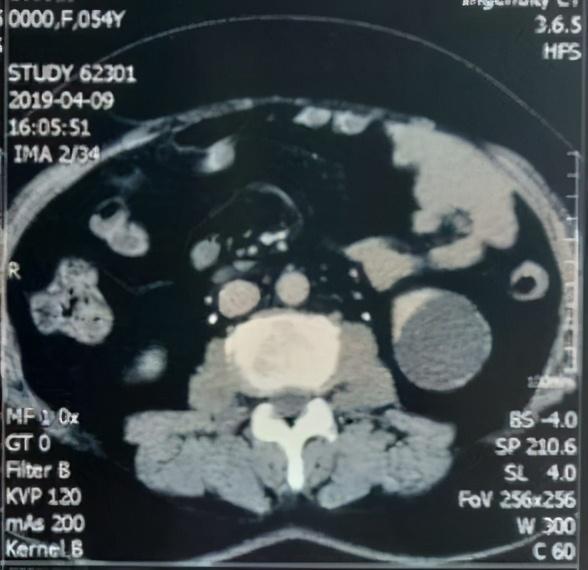

发现肾囊肿,该怎么办?需要手术治疗吗?

CT下可见左侧肾脏低密度灶,CT值与水分类似,无强化表现